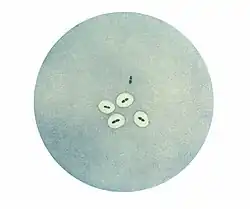

In 1900 Neufeld discovered bile solubility of pneumococci.[2] Addition of a small amount of ox bile to a pneumococcal culture results in complete destruction of the culture after a short incubation. This unique property became widely used to diagnose pneumococcal infections. Then, using immunological techniques, Neufeld discovered that there were three pneumococcal types. In the presence of type I antiserum type I pneumococci would swell, likewise types II and III in the presence of their specific antisera. Neufeld called this the quellung reaction, after the German word for swelling.[3][4] The quellung reaction allowed for easy laboratory identification of pneumococcal types.[5] Using Neufeld’s discoveries, Fred Griffith showed that pneumococci could transfer genetic information and transform one type into another.[6] Oswald Avery then found that the transforming substance was DNA. All of modern molecular biology has evolved from this work.

Photomicrograph of pneumococci revealing capsular swelling using the Neufeld quellung test.